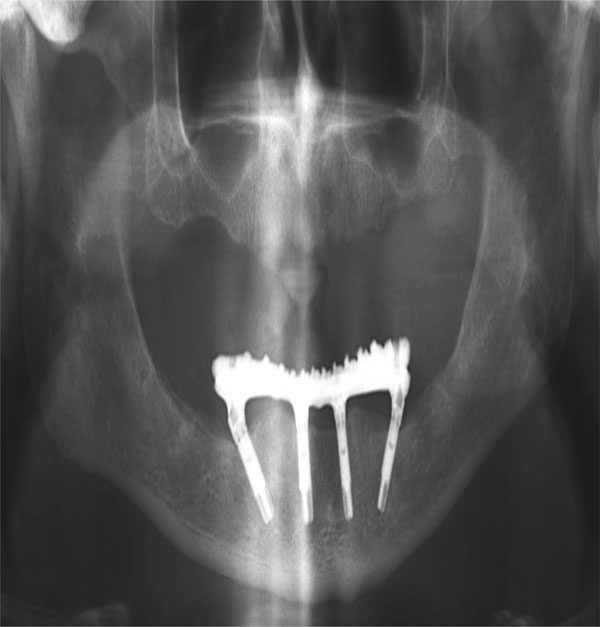

Introduced by Malo´ et al. in 2003, the All on 4 concept involves the use of 4 implants, including 2 distally tilted ones in areas where bone height; nerve proximity; or the proximity of the sinus, inferior alveolar canal, and/or mental foramen have precluded the placement of axially oriented implants. In addition to preserving the relevant anatomic structures, the distal tilting allows for placement of longer implants with good cortical anchorage in optimal positions for prosthetic support. It also increases the inter-implant spaces, reduces cantilever length, and reduces the need for bone augmentation (Figs. 5and 6). Published studies on the All on 4 concept have shown cumulative survival rates to range between 92.2% and 100% [32].

Ideal implant distribution.

Prosthetic system out of distal cantilevers.